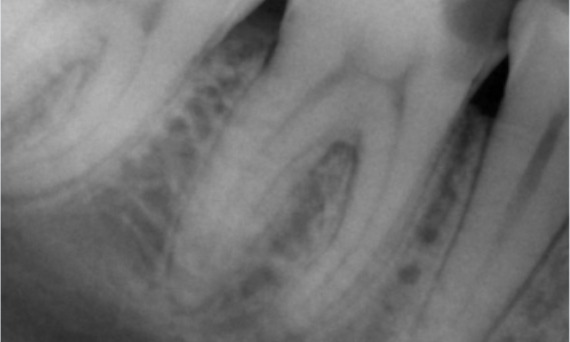

Before: Periapical radiolucency associated primarily with the distal root and loss of lamina dura on the mesial root.